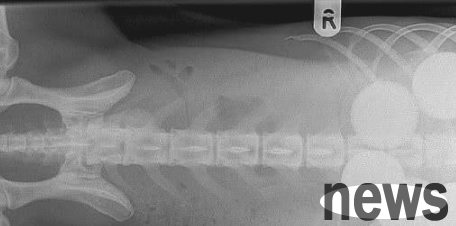

However, after half a day, the dog's abdomen still did not dissipate. The owner then realized that the dog must have swallowed something by mistake, which caused it to be unable to digest. Therefore, he took the dog to the hospital for a physical examination. It turned out that several ring-shaped things were found in the belly, but the doctor could not identify what they were in a short period of time.

After more than 2 hours of hard work, the doctor finally expelled the ring-shaped object from the dog's body. It turned out that the dog had swallowed five golf balls by mistake and was unable to digest them. Golf balls are usually made of hard rubber or plastic, not to mention that the dog also swallowed them all, so it is normal for the dog to be unable to digest them.